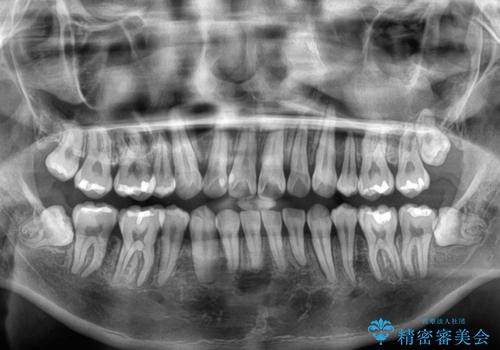

移動が順調に進み、1年半の短期間で治療を終えることができました。

前方に突出した上顎前歯の傾斜も改善されました。